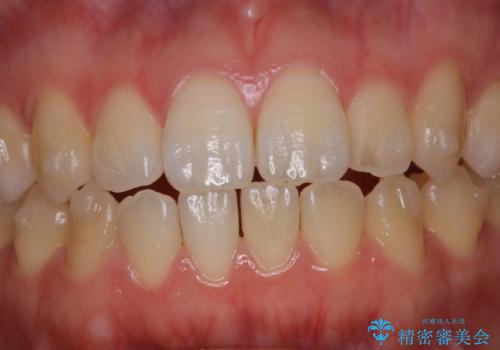

アタッチメントが歯に付くと、表面が凸凹し磨き残しが多くなったりと、プラークや歯石・着色がつきやすくなることがあります。

矯正治療中もPMTCを定期的に行い、専門的な機械でしっかりと汚れを除去することがおススメです。